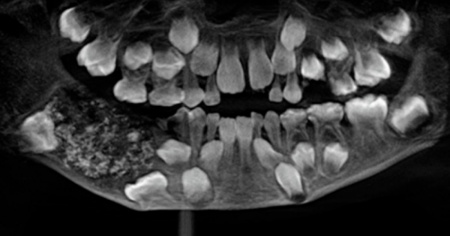

CHENNAI - I medici hanno rimosso 526 denti dalla bocca di un bambino di 7 anni. L'intervento, durato cinque ore, è stato effettuato a Chennai (India). Il piccolo paziente è stato portato al Saveetha Dental College con una mascella molto gonfia.

«Questo è il primo caso in assoluto documentato in tutto il mondo in cui sono stati trovati così tanti piccoli denti in un singolo individuo», hanno spiegato i medici. Questa condizione è nota come odontoma composto, probabilmente dovuta a un sovrannumero di germi dentari.

I denti sono stati trovati all'interno di una sacca della mascella inferiore del bambino, ogni dente aveva dimensioni variabili da 0,1 a 15 millimetri. I chirurghi hanno detto che anche il pezzo più piccolo aveva una corona, una radice e lo smalto.

«I genitori del bambino - ricostruisce il Saveetha Dental College sul proprio sito, illustrando il caso con tanto di foto - hanno fatto visitare il figlio per la prima volta in ospedale quando aveva 3 anni, dopo aver notato il gonfiore nella mascella inferiore destra. Ma il bimbo non aveva collaborato con i medici e la sua condizione all'epoca non è stata diagnosticata. Così la massa è aumentata, arrivando ad assumere i contorni di una sacca e a pesare circa 200 grammi».